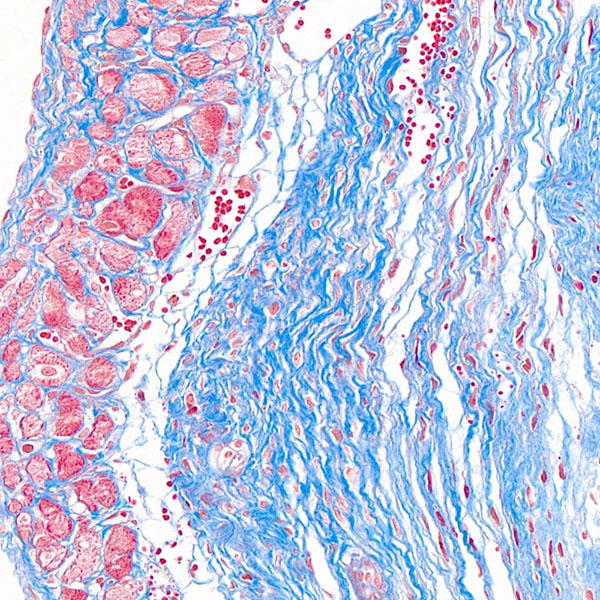

组织病理学实验

Masson染色